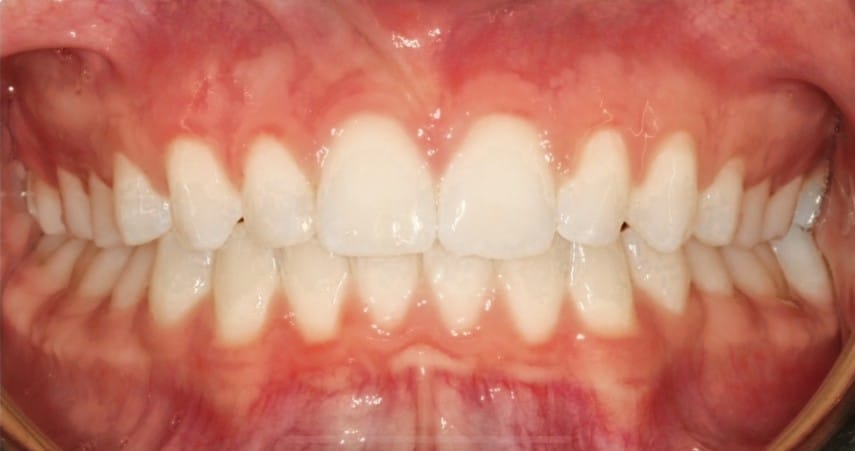

Adult patient treated with Invisalign to close excess spacing and enhance esthetics